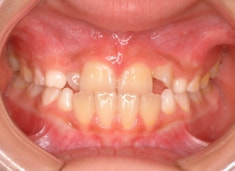

治療前